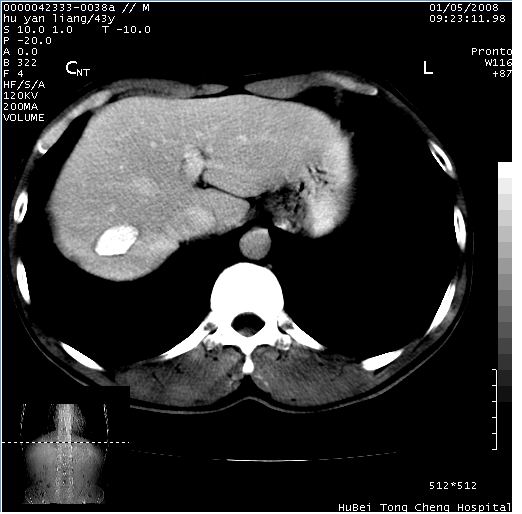

患者 男,43岁。右上腹不适1年余。既往有“肝右叶肝脓肿”病史,经保守治疗后痊愈。

b超提示:1)肝右叶肝内胆管结石。2)肝右叶占位性病变待排。

上中腹部ct轴位平扫+增强扫描(层厚10mm,螺距1.0,重建间隔10mm),图像如下:

肝右上叶偏后方较大团片状钙化灶,支持:肝脓肿后遗改变!